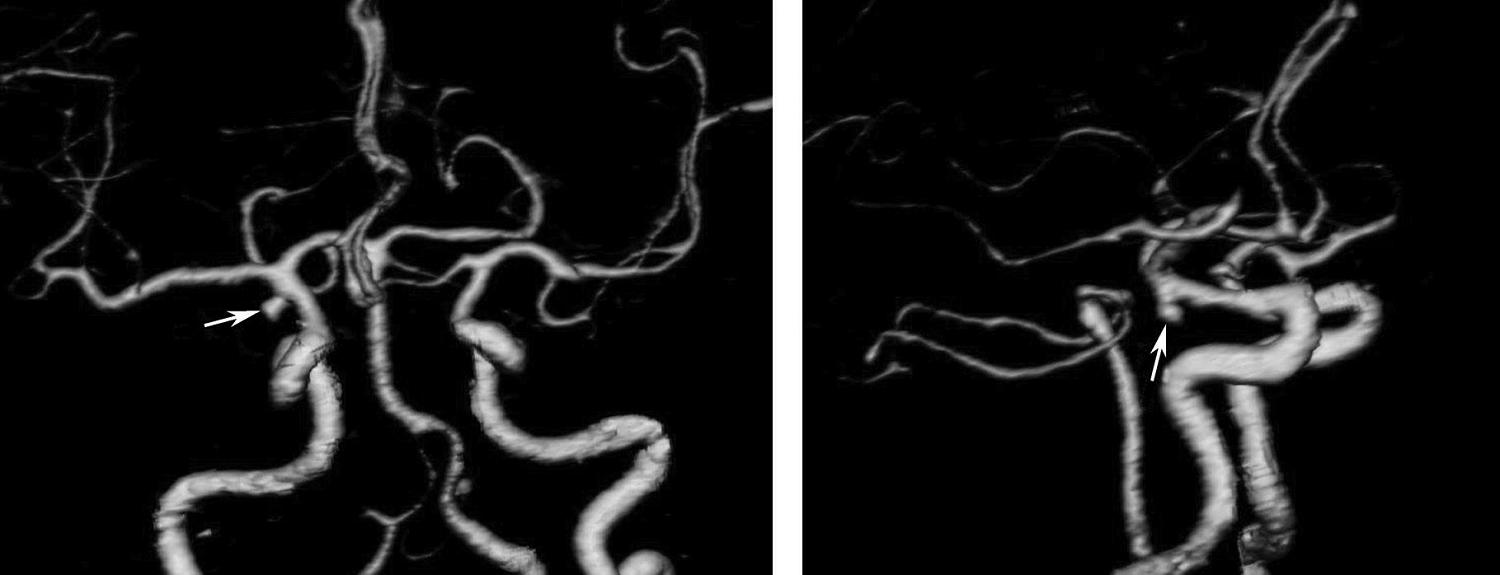

基底动脉开窗畸形的发生机制被认为是胚胎第5周时成对的胚胎性神经动脉融合障碍,或为原始侧动脉残留所致(图1-2-78)。

图1-2-78 基底动脉开窗畸形(箭)

永存三叉动脉是颈内动脉海绵窦段与基底动脉之间的胚胎性吻合,为颈内动脉系统与椎基底动脉系统之间最常见的异常交通,是根据它伴行的颅神经而命名的。其他异常吻合包括永存听动脉、永存舌下动脉及永存寰前节间动脉(图1-2-79)。

图1-2-79 永存三叉动脉

A、B.异常吻合支沟通至右侧海绵窦(箭);基底动脉(长箭)